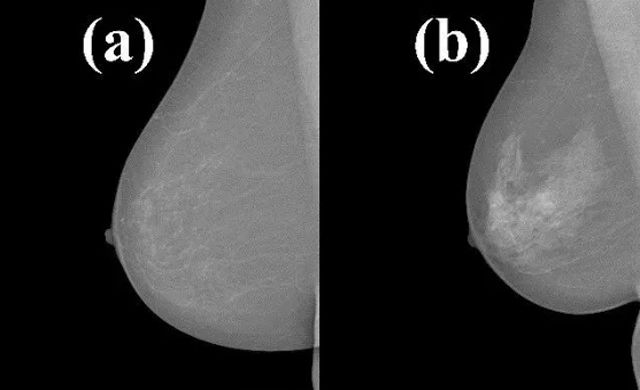

● 无惧X光:胸部本身就是有脂肪的,后天填进去的脂肪成活后,就会变成你身体的一部分,在X光下同样也同真胸一样。

【a是填充脂肪后的胸部,b是未填充脂肪的胸部】